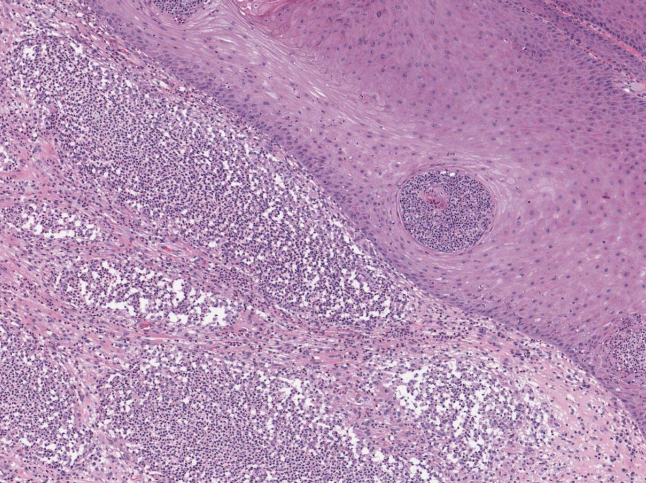

does the dermal/epidermal junction intact?

YES

what cells do you see?

plasma cells! = chronic inflammation